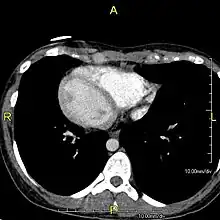

Situs inversus causes the positions of the heart and lungs to be mirrored. | |

Situs inversus is found in about 0.01% of the population, or about 1 person in 10,000. In the most common situation, situs inversus totalis, it involves complete transposition (right to left reversal) of all of the viscera. The heart is not in its usual position in the left chest, but is on the right, a condition known as dextrocardia (literally, "right-hearted"). Because the relationship between the organs is not changed, most people with situs inversus have no associated medical symptoms or complications.[1]

The condition affects all major structures within the thorax and abdomen. Generally, the organs are simply transposed through the sagittal plane. The heart is located on the right side of the thorax, the stomach and spleen on the right side of the abdomen and the liver and gall bladder on the left side. The heart's normal right atrium occurs on the left, and the left atrium is on the right. The lung anatomy is reversed and the left lung has three lobes while the right lung has two lobes. The intestines and other internal structures are also reversed from the normal, and the blood vessels, nerves, and lymphatics are also transposed.

If the heart is swapped to the right side of the thorax, it is known as "situs inversus with dextrocardia" or "situs inversus totalis". If the heart remains on the normal left side of the thorax, a much rarer condition (1 in 2,000,000 of the general population), it is known as "situs inversus with levocardia" or "situs inversus incompletus".

Diagnosis of situs inversus can be made using imaging techniques such as x-ray, ultrasound, CT scan, and magnetic resonance imaging (MRI).[7]